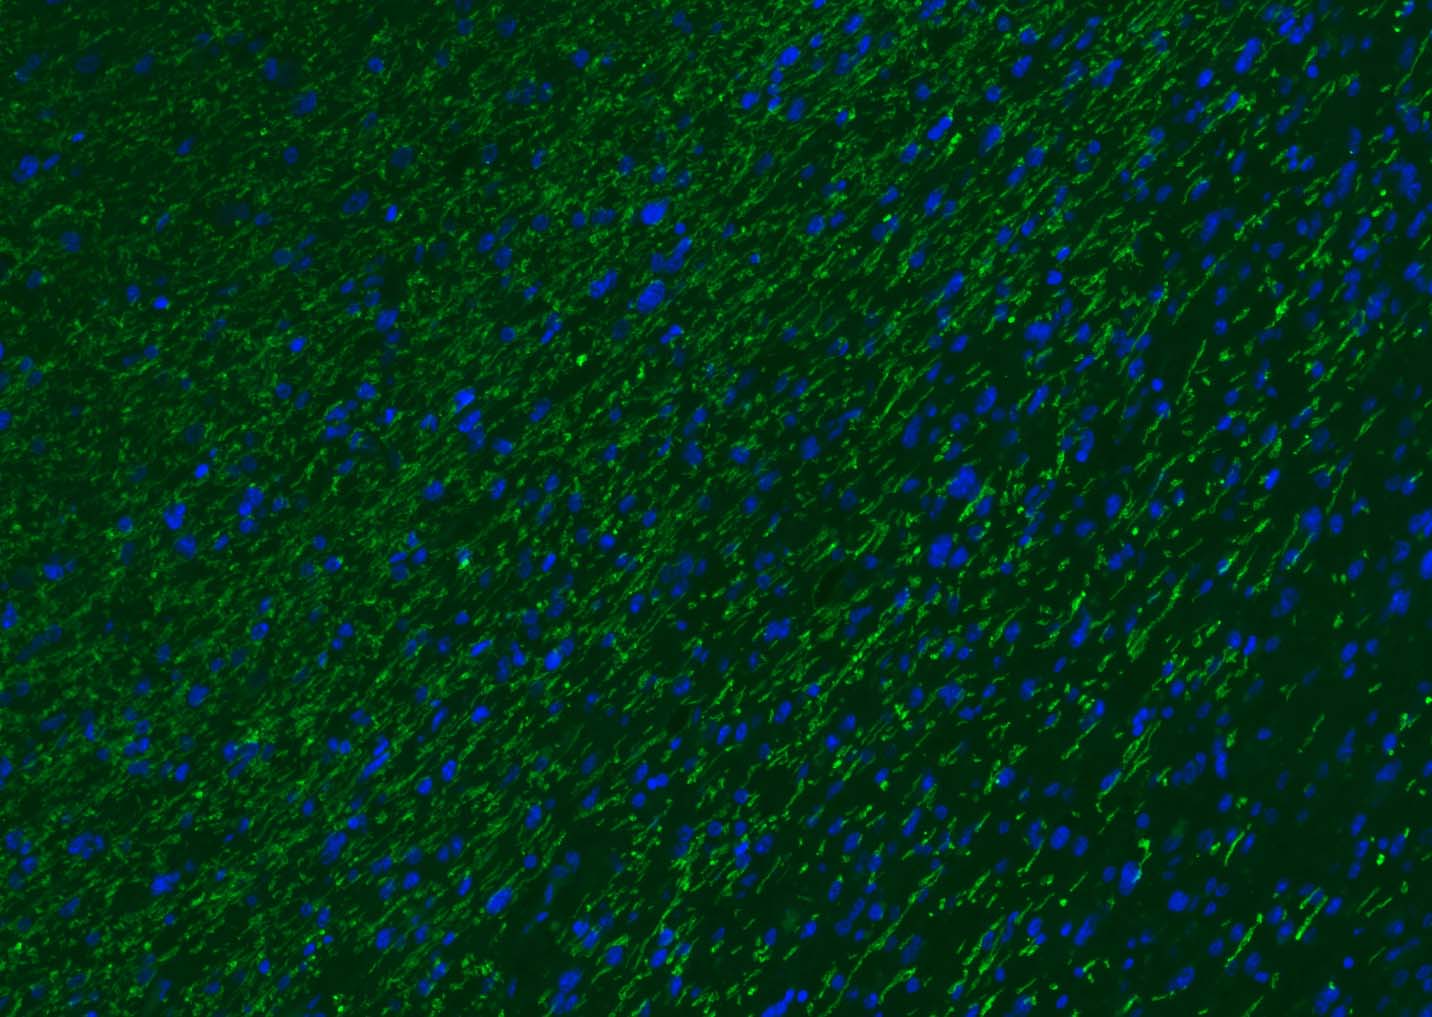

The protein encoded by the classic MBP gene is a major constituent of the myelin sheath of oligodendrocytes and Schwann cells in the nervous system. However, MBP-related transcripts are also present in the bone marrow and the immune system. These mRNAs arise from the long MBP gene (otherwise called "Golli-MBP") that contains 3 additional exons located upstream of the classic MBP exons. Alternative splicing from the Golli and the MBP transcription start sites gives rise to 2 sets of MBP-related transcripts and gene products. The Golli mRNAs contain 3 exons unique to Golli-MBP, spliced in-frame to 1 or more MBP exons. They encode hybrid proteins that have N-terminal Golli aa sequence linked to MBP aa sequence. The second family of transcripts contain only MBP exons and produce the well characterized myelin basic proteins. This complex gene structure is conserved among species suggesting that the MBP transcription unit is an integral part of the Golli transcription unit and that this arrangement is important for the function and/or regulation of these genes.

| IF | Human, Mouse, Rat | Rabbit, Pig, Sheep, Cow, Dog, Horse | 1:500-2000 |